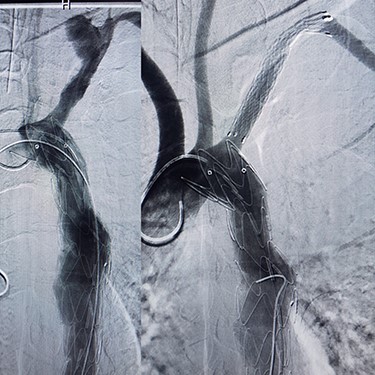

Case 3 – A 44-year-old man, known case of BD, who underwent open surgery for right common iliac artery aneurysm 1 year ago. The patient was referred to our hospital with a huge pulsatile neck mass. The right femoral artery pulse was absent in physical examination. CTA showed the iliac graft was thrombosed, but his lower limb did not have symptoms of ischemia. Corticosteroid therapy was prescribed before starting the procedure. In addition, a left carotid artery aneurysm was identified (Fig. 4A), so a stent-graft was inserted in the left common carotid (Fig. 4B). The pulsation and bruit of the mass disappeared immediately after the procedure and patient was discharged without complications. After 1-year follow-up, there was no sign of pseudo-aneurysm and the stent-graft was open.

(A) Carotid angiography before stent-graft placement (left), (B) after stent-graft placement (right).